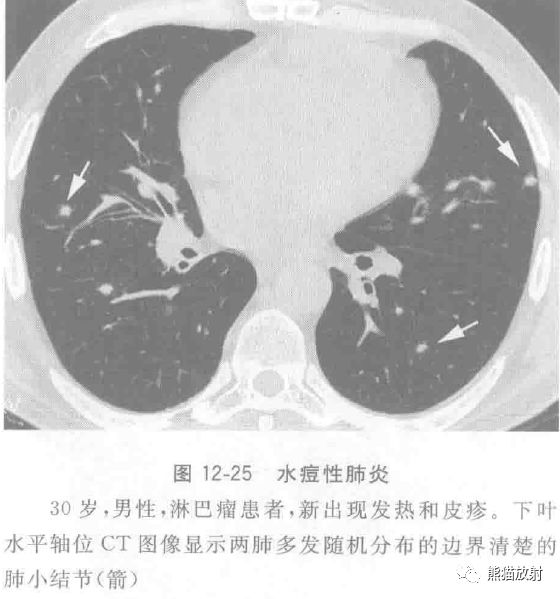

水痘-带状疱疹病毒感染常见于儿童,具有传染性,成人感染也日渐增多。临床表现有两种类型:一种为水痘,发生在既往未感染过的个体,并具有传染性;一种为带状疱疹,为潜伏的病毒再次激活,表现为单侧皮肤皮疹。

成人感染水痘最严重的并发症是肺炎,但较少见。据报道,约每400例成人感染水痘患者中有一例并发水痘肺炎,在孕妇及免疫抑制患者中更常见。薄层CT表现为多发直径为5~10mm的结节灶(图12-25),部分结节周围有磨玻璃样晕环,斑片状磨玻璃影和聚集的结节。偶见病变钙化,表现为边界清楚,散在分布的直径2~3mm的致密钙化结节。